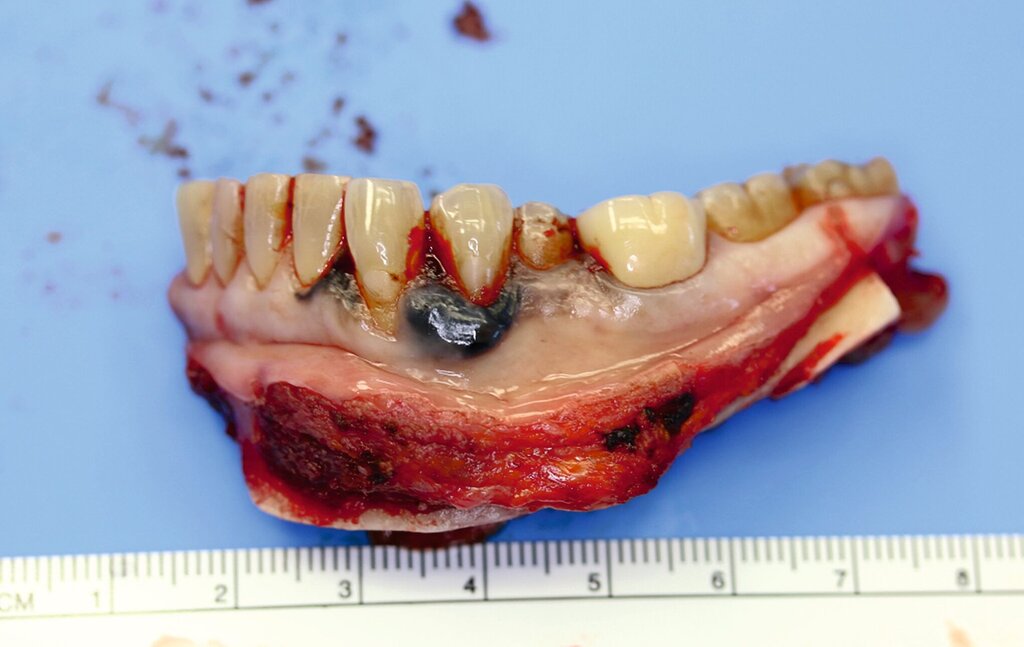

Eine im Januar 2024 alio loco durchgeführte Probenentnahme ergab eine resorptive Entzündung mit Pigmenteinlagerungen. Die Patientin berichtet, dass die Schleimhautveränderung etwa vier Wochen vor der Vorstellung bei uns begonnen habe zu wuchern. Klinisch zeigte sich eine 10 mm x 7 mm messende, exophytisch wachsende, schwarz pigmentierte Raumforderung (Abbildungen 1 und 2). Durch eine Probenentnahme in domo konnte histopathologisch ein malignes Melanom gesichert werden.

Die prätherapeutische Fallvorstellung im interdisziplinären Hauttumorboard ergab die Empfehlung zur primären Resektion und zu einer Halslymphknotenentfernung der Level I–III beidseits. Diese erfolgte im Sinne einer kontinuitätserhaltenden Unterkieferteilresektion (Abbildungen 4 bis 6). Die Rekonstruktion erfolgte durch ein mikrochirurgisch anastomosiertes, fasziokutanes Radialistransplantat vom linken Unterarm. Der Entnahmedefekt wurde mittels Vollhaut vom linken Unterarm gedeckt. Zudem wurde eine beidseitige selektive Halslymphknotenausräumung in Level IA, IB, IIA, IIB und III durchgeführt. Die Patientin konnte in gutem Allgemeinzustand am 15. postoperativen Tag entlassen werden.